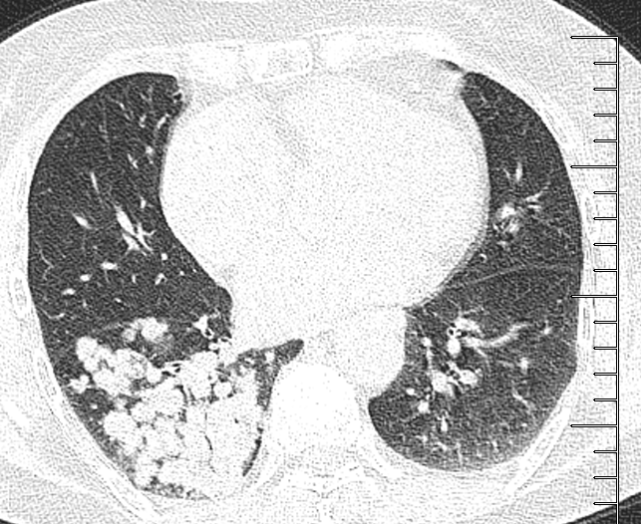

支气管痰栓,支气管充气征

且长时间无法咳出,最终形成了固体的痰栓,堵在了支气管内,往往需要

反复于外院就诊,诊断为"支气管扩张合并痰栓形成,咯血",给予抗感染

支气管,肺结核并粘液栓,与先天性支气管闭锁的鉴别